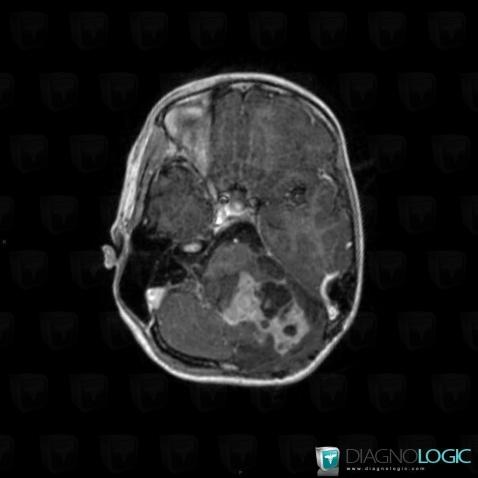

Gangliocytoma, Cerebellar hemisphere, Posterior fossa, MRI

Here is the specific information in the key image above:

- Diagnosis Gangliocytoma, Location(s) Posterior fossa, with gamuts Infratentorial lesion with intense enhancementCerebellar hemisphere, with gamuts Cerebellar lesion